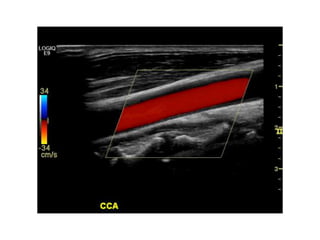

Color Flow (CF)

A Primer ofDiagnostic Ultrasonic Imaging Modalities Doppler modes Color Flow (CF)